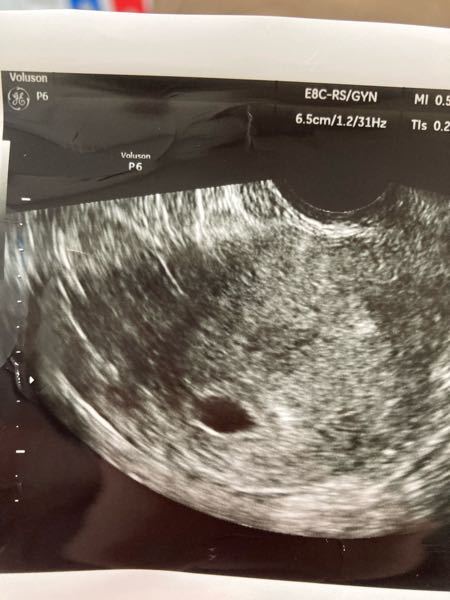

エコーの見方を教えてください。 - 胎嚢確認できたのですが、大きさ